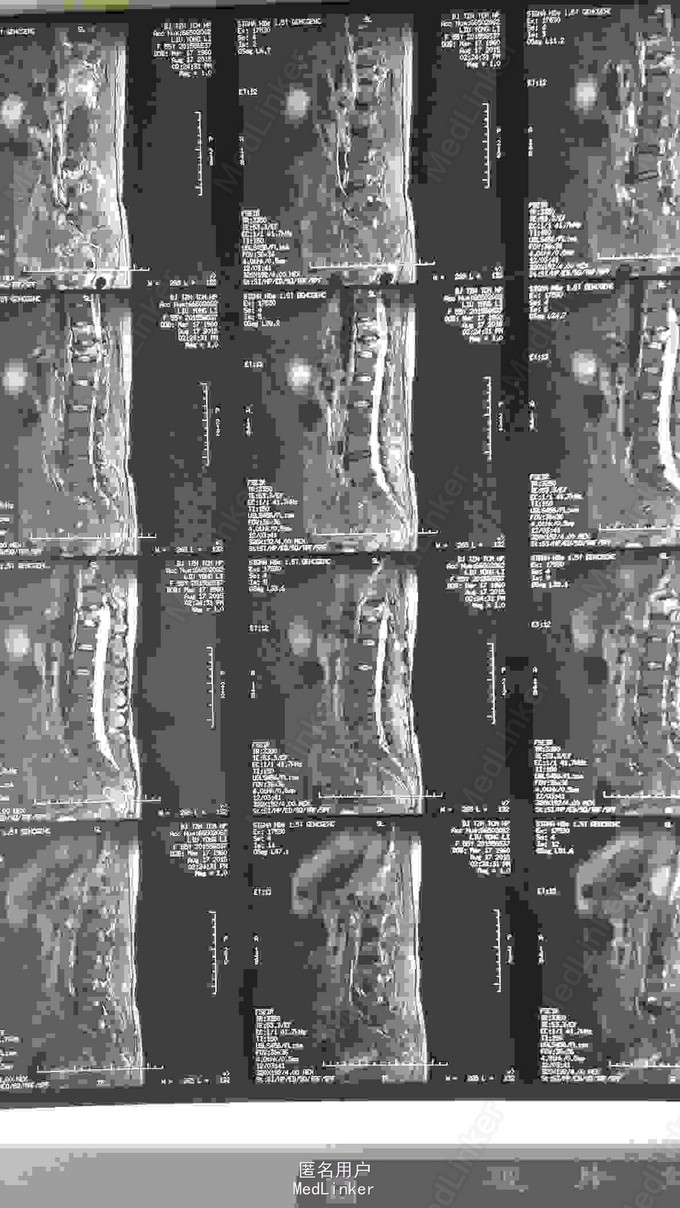

胸椎压缩骨折

患者,女性,55岁,主因外伤致胸背部疼痛3天入院

胸背部压痛及叩痛阳性,双下肢感觉运动血运良好。

胸11,12压缩骨折,行胸11,12pkp治疗后,患者腰背部疼痛明显缓解。